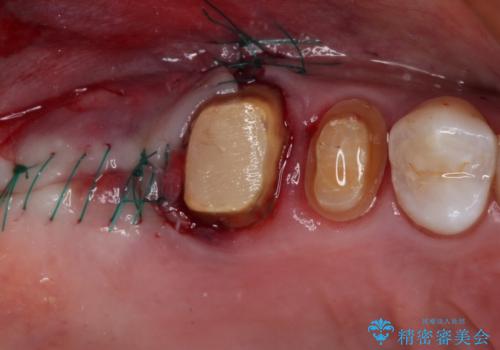

不安定な咬み合わせとなっており、クラウンの表面が剥離していたため、インプラントによる欠損補綴治療を行い、手前2つの歯も一緒に補綴治療を行うこととしました。

治療中の仮歯も頻繁に壊れておりましたが、インプラントの土台が歯肉上に出てからは咬み合わせが安定し、仮歯が壊れることもなくなりました。